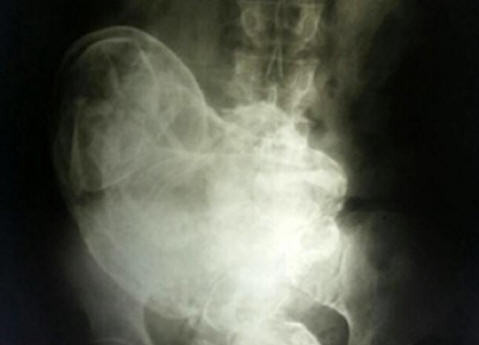

84-vuotiaan brasilialaisen naisen kohdussa löydettiin murtunut sikiö 44-vuotias. Tämä tapahtui sietämättömyyden vuoksi vatsakipu nainen otti yhteyttä lääkäriin, joka teki hänestä X-ray. Kuvassa he näkivät sulautuneen alkion. Tämä ilmiö sai lääketieteellisessä käytössä nimen litopedion. Lithopedion – kivettynyt kohdun sikiö, joka on kuollut kohtuun tai vatsan ontelo, jolle sitten tehtiin kalkinmuutos. Se on harvinaista ilmiö, joka esiintyy pääasiassa sikiön kuollessa kohdunulkoinen raskaus. Koska ei ole luonnollista tapa päästä eroon sellaisesta sikiöstä, keho paljastaa sen kalsiumia estävän sikiökudoksen vahingoittumisen estämiseksi kantajan runko. Naista tutkineet lääkärit päättelivät että sikiö kuoli 28. raskausviikolla. Siitä huolimatta leikkauksesta potilas kieltäytyi poistamasta sitä. Marokon tapaus Tämä ilmiö on hyvin harvinainen, joten yleensä esiintyy tapauksia sen esiintymisestä historioitsijoiden kirjaama. Tätä kuvataan vuonna 2012. Asukas pieni kylä, joka sijaitsee Casablancan lähellä, Marokko, kolmen lapsen äiti Zahra Abutalib viimeksi tuli raskaaksi 26-vuotiaana. Yhdeksän raskauskuukautta sikiö kulki ilman komplikaatioita. Sairaalassa hänestä tuli kuitenkin todistaja kuolema sairaalan kämppiksessä, nuori äiti, joka kuoli leikkauspöydällä keisarileikkauksen seurauksena. ei onnistui pelastamaan lapsensa. Pelkää, että tällainen kohtalo voi odottaa häntä, vaikuttava Zahra, keräämässä asioita, pakeni sairaalat, jotka päättävät synnyttää kotona. Seuraavien parien aikana päivää hän kärsi kauhistuttavasti syntymäkipuista, kuitenkin kauan odotetusta lapsi ei koskaan tullut maailmaan. Hän lopetti pian kokonaan liikkua kohdussa, ja nainen päätti, että vauva “nukahti”. Zahra muisti hyvin paikallisen myytin “nukkuvasta vauvasta”. Väitetään, jos ei synnyttää hänet, niin hän puolustaa äitinsä kunnia koko elämänsä ajan. Siksi ei erityisen huolissaan hänen tilasta, etenkin supistumisten takia ei enää toistettu. Tämä jatkui neljäkymmentäkuusi vuotta, kunnes äskettäin, jo 75-vuotiaana, kipu ei palannut yhtäkkiä. Zahra kääntyi lääkäreiden puoleen. Ultraääntutkimus kaupungin sairaalassa Rabat osoitti vieraan naisen läsnäolon vatsassa ruumiit, joiden alkuperää lääkärit eivät voineet selittää. se oli suoritti kehon perusteellisemman tutkimuksen tulosten perusteella jonka asiantuntijat päättelivät, että kiinteä massa kehossa Zahra ei ole muuta kuin kivettynyt hedelmä, joka on naisen vartalo ihmeellisesti erehtynyt elimeen ja siksi pitkään aikaan pidetään vieraana kehona. Leikkaus kesti neljä tuntia. Lopulta lääkäreiden ryhmä, jota johtaa Dr. Taibi Kuazzani onnistui uuttamaan naisen kehosta sikiön, joka painaa hieman yli kaksi kiloa ja pituus 42 senttimetriä. Joten melkein puoli vuosisataa Zahran vauva syntyi lopulta.

Kuva avoimista lähteistä. Litopedioni muodostuu naisen vartaloon sikiön kuolema, yleensä kohdunulkoisen synnytyksen jälkeen raskaus, vaikkakin on tapauksia sen muodostumisesta kohtuun. Äidin ruumis näkee kuolleen lapsen vieraana kehona, ja suojaavan reaktion seurauksena sikiö muumioituu. ensimmäinen yksityiskohtainen kuvaus tällaisesta tapauksesta on peräisin vuodelta 1582, kun tietty Ranskalainen lääkäri löysi 68-vuotiaan naisen ruumiinavauksen kivettyneet hedelmät, jotka pysyivät äidin kohdussa 40 vuotta. Elinikäinen raskaus Lääketieteellisten tilastojen mukaan “kivilapset” voivat pysyä ihmisen sisällä niin kauan kuin pitkään. Ja 46 vuotta ei ole mitenkään raja. Joten, tammikuussa 2009 vuonna sairaala Kiinan Huangiaotangin kaupungissa, josta tuli 92-vuotias asukas Huang Yuijun, joka valitti erittäin voimakkaasta kipusta vatsa. Mikä oli lääkäreiden yllätys, kun he huomasivat sen vanha nainen … raskaana! Lisäksi raskaana pitkään – 60-vuotias! Hänen hämmästyttävä tarinansa The Sunin mukaan on alkanut vuonna 1948. Sitten lääkärit kertoivat Huangille, että sikiö oli kuollut aiemmin syntymä hänen kohdussaan. Sen poistamiseksi tarvittiin toimenpide jonka lääkärit pyysivät summaa paikallisessa valuutassa vastaavana 150 dollaria. Kuultuaan hinnat, Huang vain kääntyi ympäri ja lähti. “Tämä on tuolloin oli paljon rahaa, nainen sanoo, enemmän kuin kaikki perheeni jäsenet ansaitsivat muutamassa vuodessa. Siksi minä En tehnyt mitään, päättäessään sivuuttaa lääketieteellisen diagnoosin. ” “Huomiotta jättäminen” jatkui useita vuosikymmeniä, kunnes kuollut vuonna 2003 kohdussa, lapsi ei muistuttanut itseään uudestaan. “En voinut uskoa omille silmilleen, kun hän huomasi, että kohdussa Yuijun on lapsi ”, sanoo tohtori Liu An Bin Gwingshengin sairaalasta. – varten 40 vuoden harjoittelu lääkärinäni ei ole enempää En ole nähnyt mitään outoa tai yllättävää. ” Synnytyslääketieteen ja gynekologian sairaala Xu Xiang Ming lisää: “Yleensä kuollut sikiö hajoaa sisällä. Mutta tässä tapauksessa kyse on harvinainen tapahtuma. Vielä ei ole vielä selvää, miten rouva Yuijun pysyi koko tämän ajan terveenä. “Lisää kysymyksiä aiheuttaa pisin tänään lääketieteen historiassa 93-vuotiaan Lissabonissa asuvan Maria Romandesin raskaus, joka meni sairaalaan vuonna 1996 valittaen voimakkaasta kipusta vatsa. Mikä oli lääkäreiden yllätys, kun he huomasivat sen vanha nainen on raskaana kahdella muumioituneella sikiöllä 72 vuosi! Isoäiti muistaa, että vuonna 1924 hän sairastui sairas, hän painoi. Samalla havaittiin pysähdys kuukautiskierron aikana. Nainen tajusi, että hänellä oli jonkinlainen ongelma naisten puolella, mutta koska en tuntenut erityisen voimakkaita kipuja, En myöskään mennyt lääkärin puoleen. Jonkin ajan kuluttua, pahoinvointi ohi, ja Maria valitti terveydestään vasta keväällä 1996 vuosi. Saatuaan selville “taudin” syyn lääkärit viipymättä hänellä oli leikkaus ja poistettiin kaksi hyvin säilynyttä tunnottomia kaksoset. Asiantuntijat uskovat kuolleen epäonnistumiseen teho. Ravitsemuksen puutteesta on tullut syy siihen Maria Romandesin ruumis ei heittänyt heitä oikeaan aikaan.